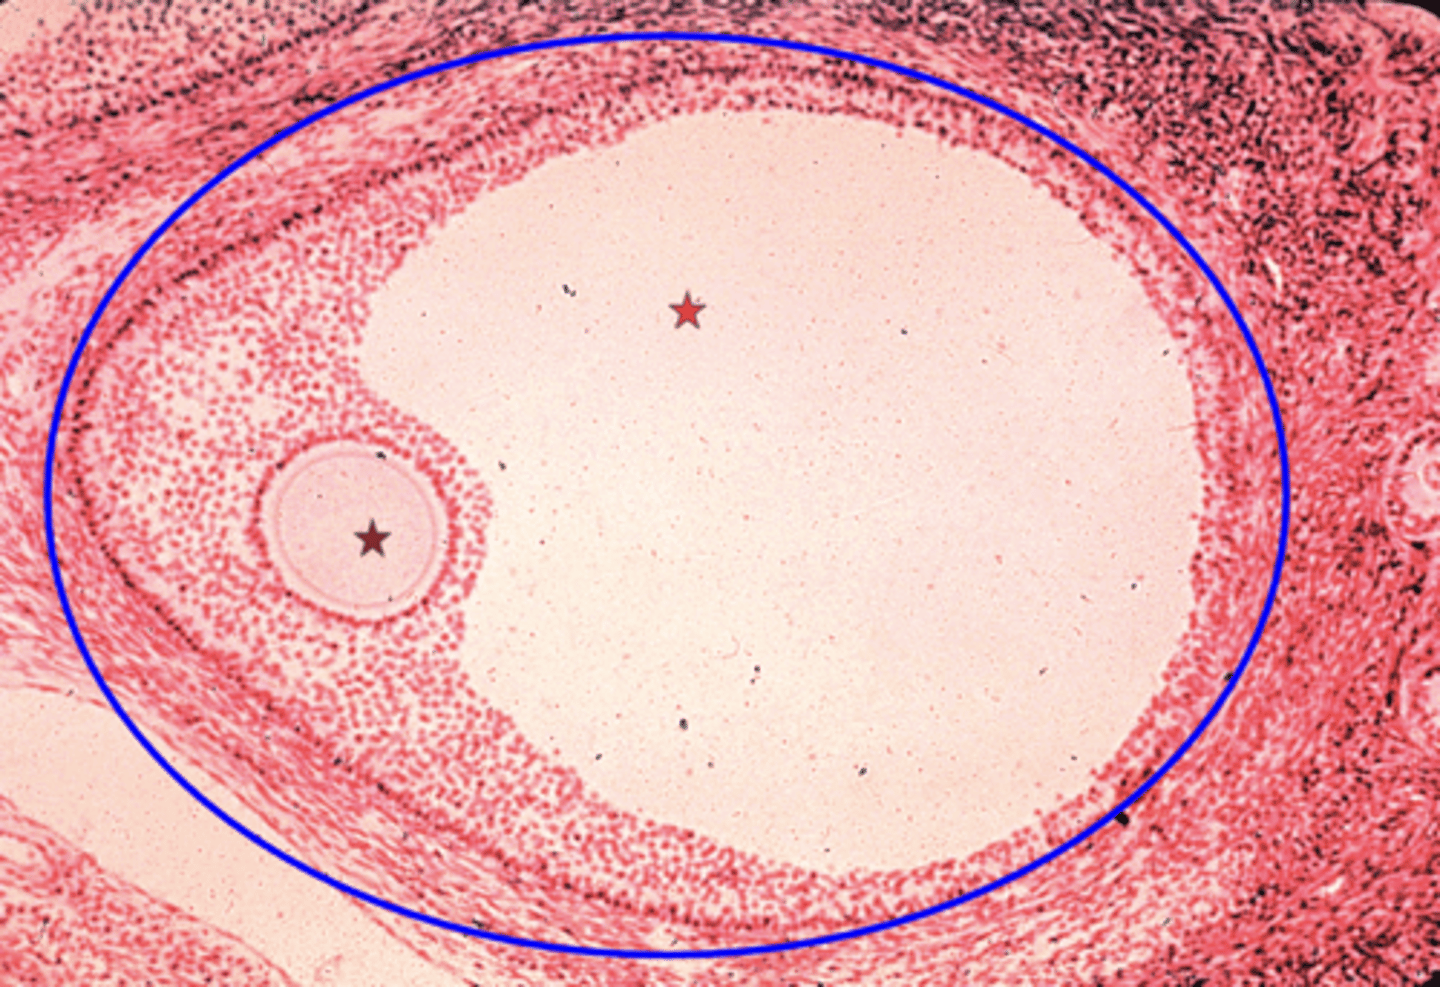

Graafian follicle

What is the blue circle?

Primary oocyte

What is the brown star?

Antrum

What is the red star?

Has a large antrum

Function of the graafian follicle?